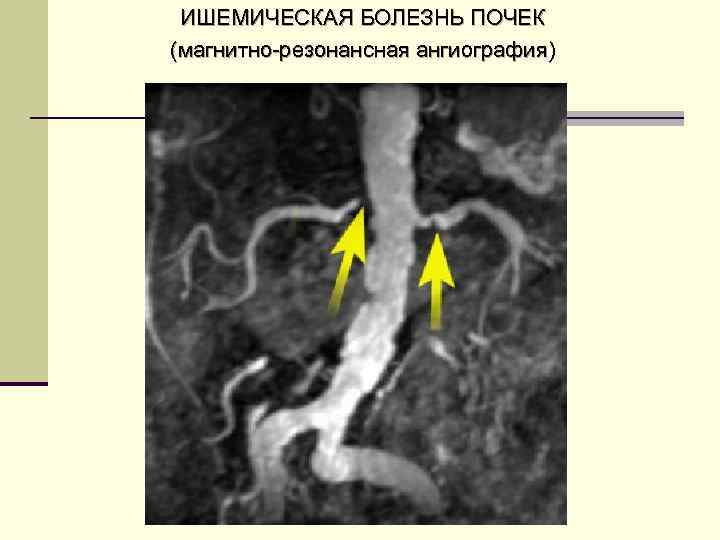

ЗАБОЛЕВАНИЯ ПОЧЕК, СОПРОВОЖДАЮЩИЕСЯ РАЗВИТИЕМ АГ II. n n n n 2 Реноваскулярные гипертензии (обусловлены стенозом почечной артерии или ишемией почки. Встречается у 1 -5% лиц с АГ, возникает при перекрытии сосуда > 50%) атеросклероз почечной артерии фибромускулярная дисплазия неспецифический аортоартериит тромбоз почечной артерии (при травме почки, ангиографии, ангиопластике) сдавление почечной артерии опухолью или кистой перегиб артерии при нефроптозе аневризма артерии пороки развития почечной артерии

ИШЕМИЧЕСКАЯ БОЛЕЗНЬ ПОЧЕК (магнитно-резонансная ангиография)